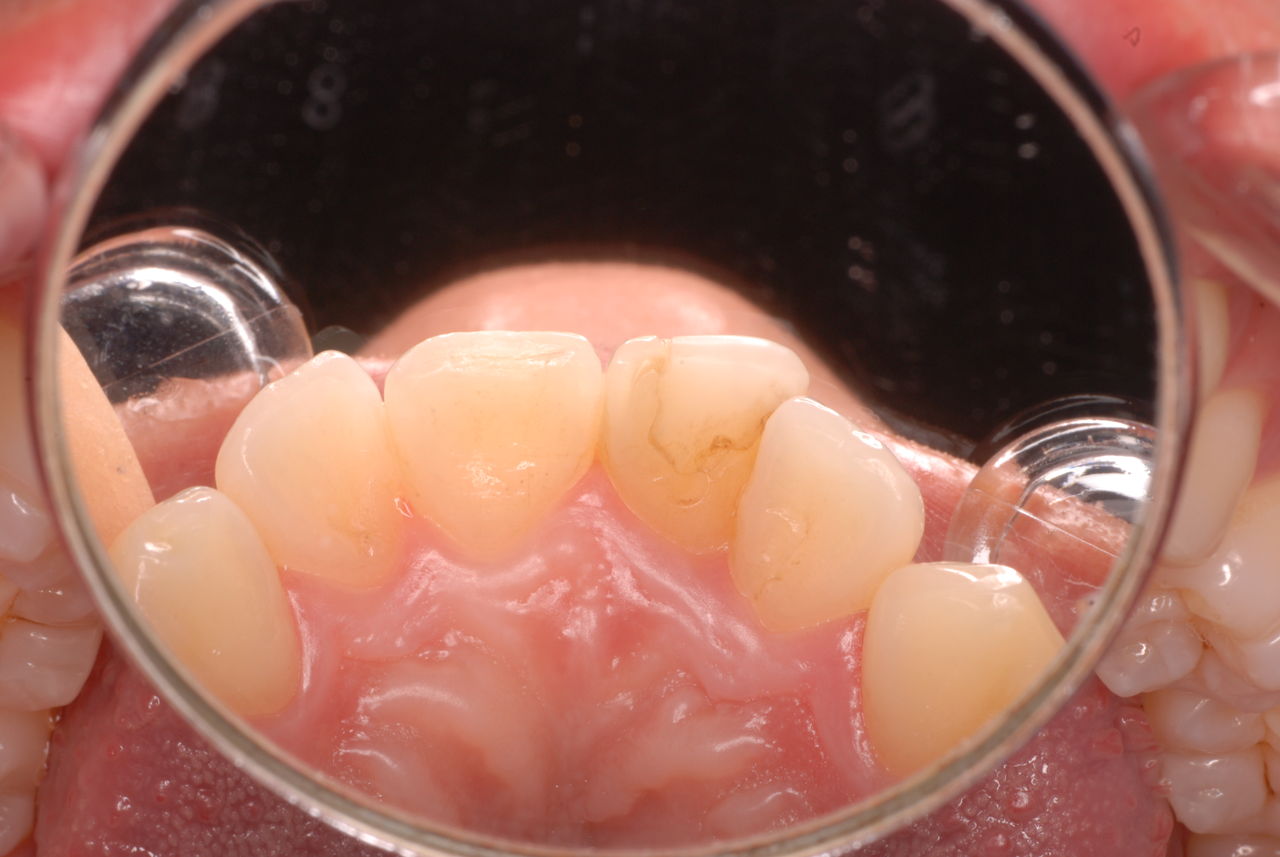

歯周病の疑いで東京のかなり遠方の方が来院されました。

驚くべきことですが、定期検診は受けていたそうです。しかしながら歯周病の指摘は受けたことがないそうです。

何故か?定期検診が虫歯のチェックのみになり、又肝心の歯周病の検査や歯周病の部分の予防や治療のためのブラシの使い方などを学んだ事がないのです。

本当に患者さんのことを考えると憂鬱になります。歯周病が悪化すると殆ど回復は無理だからです。